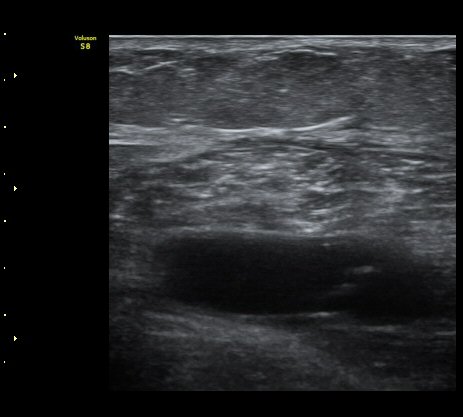

¿Ü°ß »ó ÀåµýÁö ºÎÁ¾ÀÌ °üÂûµÇ°í ³»Ãø ºñº¹±Ù¿¡ ±¹¼ÒÀû ¾ÐÅëÀ» º¸ÀÓ.

³»Ãøºñº¹±Ù°ú °¡Àڹ̱٠»çÀ̰¡ ¹ú¾îÁö°í ¼ö¾×ÀÌ Àú·ùµÊ.

ÃÊÀ½ÆÄ À¯µµÇÏ ¼ö¾× ÈíÀÎ(÷ºÎ µ¿¿µ»ó) ÈÄ ¾Ð¹ÚºØ´ë °íÁ¤.